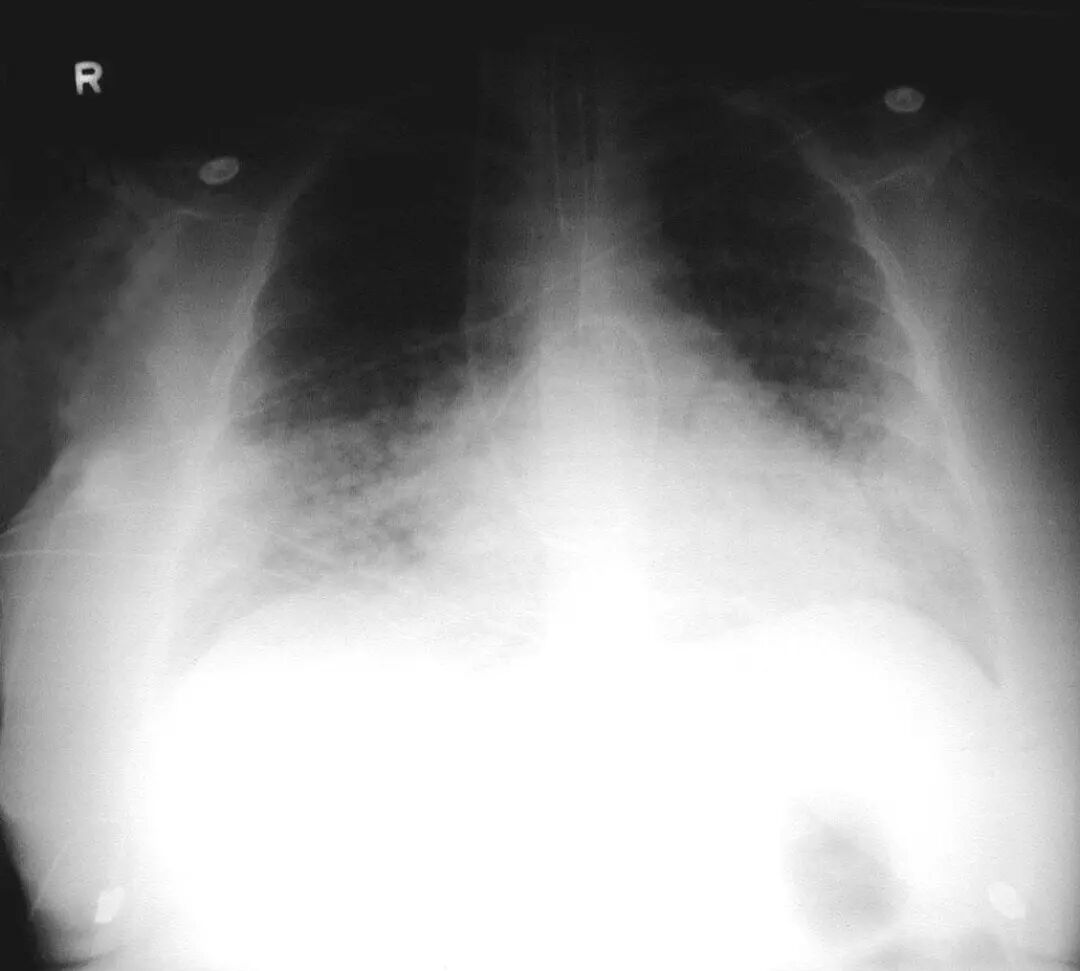

图1.4 53岁的严重军团菌肺炎患者。胸片显示双肺下叶致密实变。